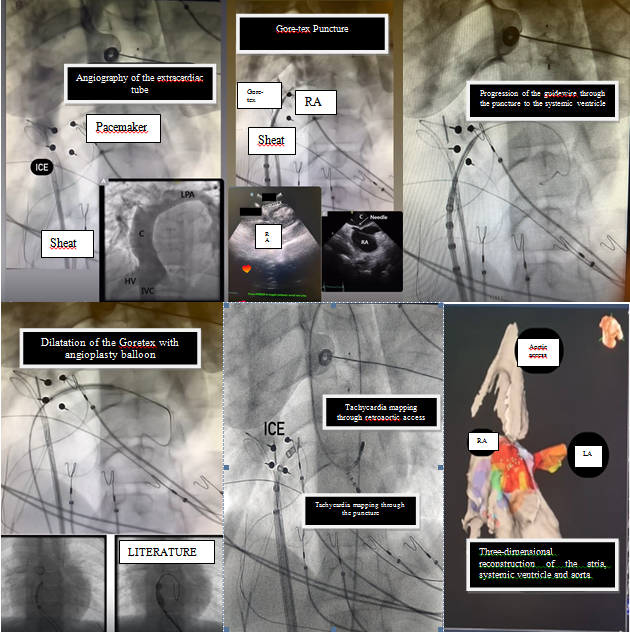

Introducción: Las indicaciones de ablación con sistema tridimensional en pacie...

Paciente masculino de 16 años de edad con diagnóstico neonatal de doble salida...